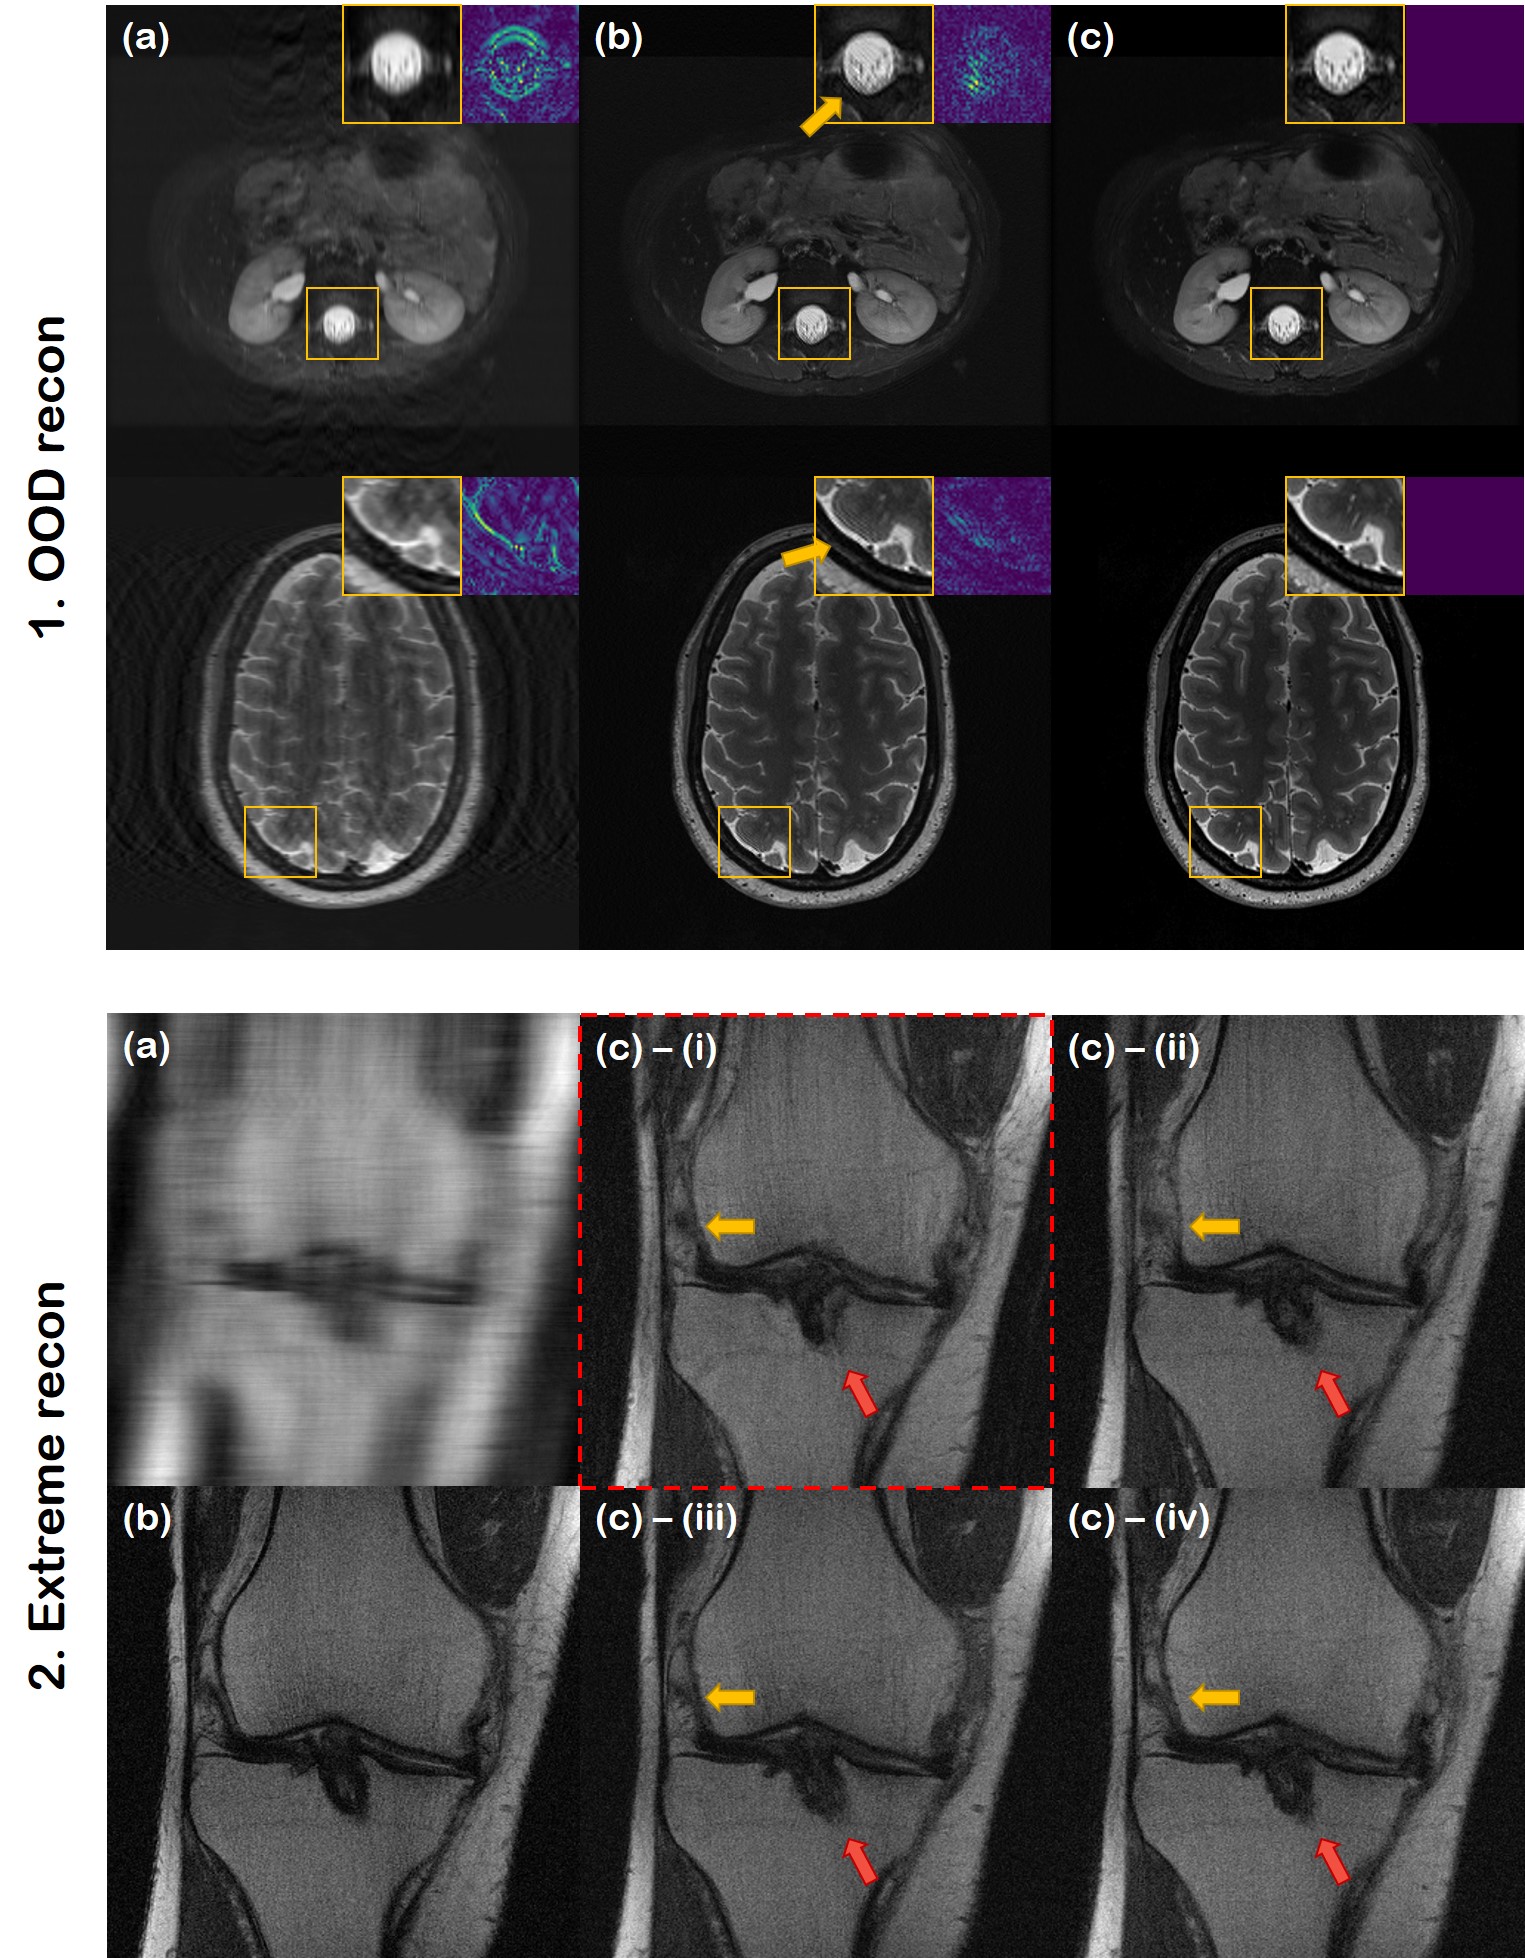

5.6 Reconstruction out-of-distribution (OOD) data

Refer to caption

Fig. 9: Reconstruction results of various anatomic structure/contrast. (a) TV, (b) U-Net, (c) DuDoRNet, (d) proposed method, (e) ground truth. 1st row: HCP axial brain scan, 2nd row: MRI scan of left leg collected from [16], 3rd row: axial knee scan from [16], 4th row: MASSIVE coronal brain scan. 1D Gaussian ×4absent4\times 4 under-sampling was performed.

In Fig. 9, we present reconstruction results, which are heavily out of distribution. Note that our score function has only learnt the distribution of proton density (PD) / proton density fat suppression (PDFS) coronal knee scans. Nevertheless, we observe that with the proposed method, we are able to achieve high fidelity reconstructions regardless of the anatomy and contrast. While other methods such as U-Net and DuDoRNet generalizes to a certain extent, we can clearly observe leftover aliasing artifacts. On the other hand, the proposed method clearly outperforms all the other methods with minimal residuals and sharp contrast. We recently found that this observation was also made independently in [23], where the authors partially proved that posterior sampling is indeed highly robust to distribution shifts. This property is indeed very advantageous in real-world settings, since one may be able to use a single neural network regardless of the specific anatomy and contrast. For further experimental results of different anatomy, please see Fig. 14 and Fig. 15 in the Appendix.